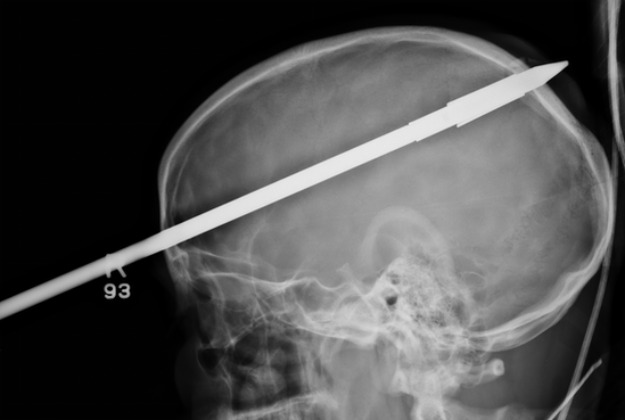

Pravo medicinsko čudo - tako su američki ljekari nazvali tinejdžera koji je preživio trosatnu operaciju odstranjivanja koplja koje mu je doslovno probilo mozak

KOPLJE KROZ GLAVUYasser Lopez, 16-godišnjak s Floride, uspješno se oporavlja od zahtjevne operacije u bolnici u Miamiju, javlja BBC.

Kako su potvrdili ljekari, tinejdžer je tokom izleta ranije ovog mjeseca pogođen kopljem dužine 90 centimetara ravno u glavu, tačnije, u područje iznad desnog oka.

Nakon trosatne operacije, kojom mu je koplje odstranjeno iz glave, tinejdžer se uspješno oporavlja. Probudio se i potpuno normalno komunicira s okolinom. 16-godišnjak se, prema izjavama ljekara, ne sjeća nesreće, prenosi Index.hr.